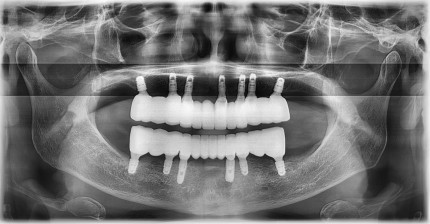

쿨쿨플란트치과 전악임플란트 치료 전후사진